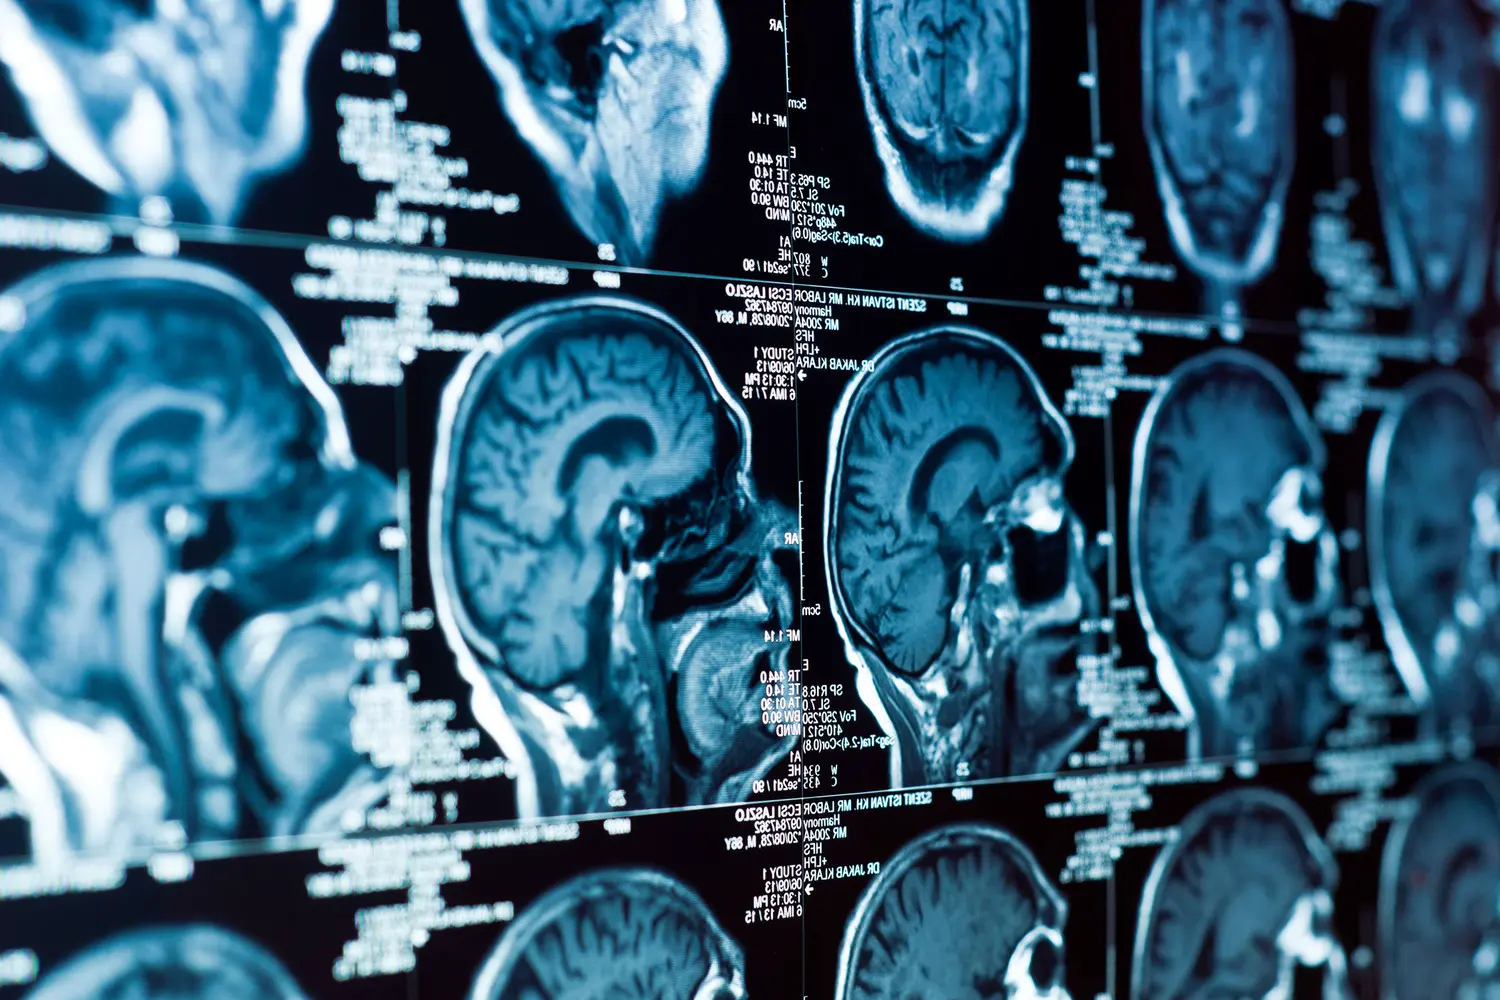

Влияние загрязнения воздуха на благополучие центральной нервной системы

Современные исследования подтверждают значимую роль чистого воздуха для сохранения здоровья головного мозга. Группа специалистов из Датского института рака в Копенгагене под руководством Уллы Хвидтфельдт представила новые данные об опасности загрязненного городского воздуха для мозговых тканей.